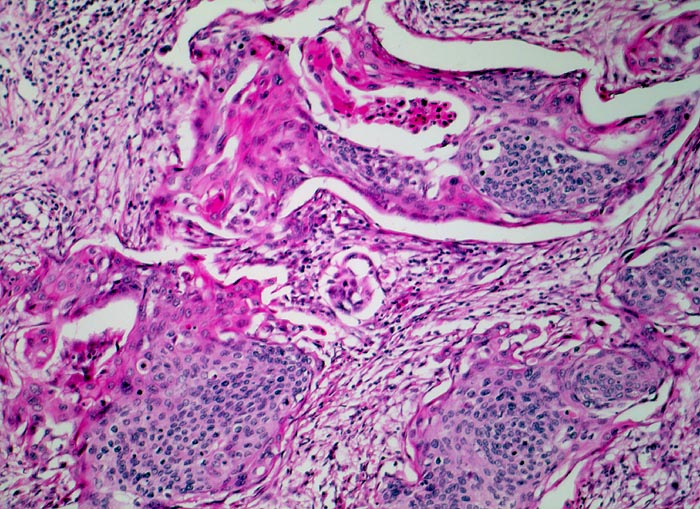

Invasives Plattenepithelkarzinom der Zervix

Unregelmässig begrenzte Tumorzellstränge liegen in einem lockeren desmoplastischen Tumorstroma. Ein Teil der Tumorzellen zeigt eine deutliche plattenepitheliale Differenzierung mit reichlich hypereosinophilem Zytoplasma.

Im Portioabstrich anlässlich einer gynäkologischen Kontrolle Pap V, Hysterektomie

Histologie

100